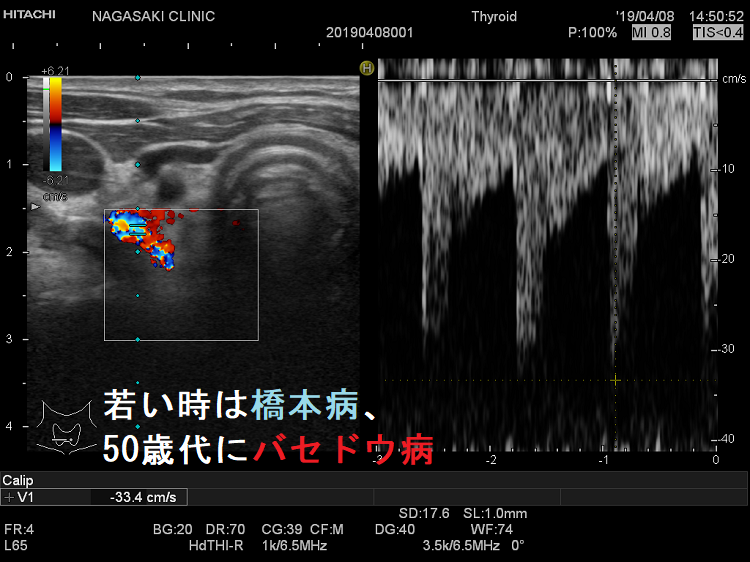

よくあるパターンは「若い時、バセドウ。齢(とし)いって橋本」と言うやつです。(当然、逆もあり)

上條甲状腺クリニックの統計では、

- 橋本病(慢性甲状腺炎)の2.2%が、甲状腺機能亢進症/バセドウ病に移行(「上條甲状腺クリニックの甲状腺疾患Q&A」より)

30歳代・50歳代に2相性ピークがあり、出産後甲状腺炎・喫煙が関与するとされます。

- 甲状腺機能亢進症/バセドウ病の12.2%は橋本病(慢性甲状腺炎)からの移行です。「上條甲状腺クリニックの甲状腺疾患Q&A」より